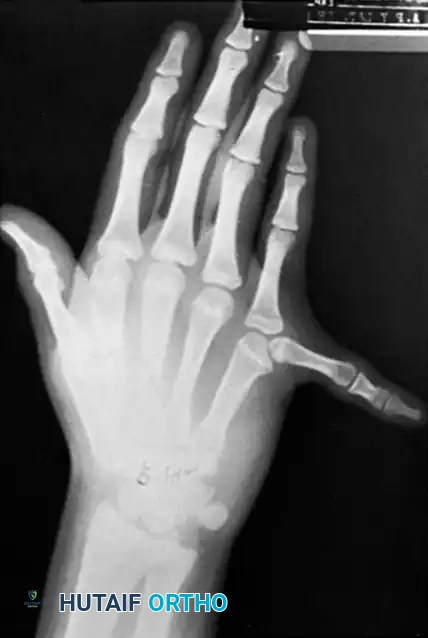

Fig. 76-43 Bifid thumb. A and B, Type II duplication demonstrating partial bifurcation at the distal phalanx.

Fig. 76-43 Bifid thumb. C and D, Type IV duplication (the most common variant), showing complete duplication of the proximal and distal phalanges.

The Wassel Classification

Wassel’s classification system (1969) remains the universal standard for categorizing thumb polydactyly based on the level of skeletal bifurcation.

- Type I: Partial duplication of the distal phalanx with a common epiphysis.

- Type II: Complete duplication of the distal phalanx, including its epiphysis.

- Type III: Duplication of the distal phalanx with bifurcation of the proximal phalanx.

- Type IV: Complete duplication of both the distal and proximal phalanges (Most common: 47%).

- Type V: Complete duplication of the distal and proximal phalanges with bifurcation of the metacarpal.

- Type VI: Complete duplication of the distal and proximal phalanges and the metacarpal.

- Type VII: Variable degrees of duplication associated with a triphalangeal thumb (20%).